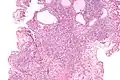

Micrograph of a nephrogenic adenoma. H&E stain. | |

Nephrogenic adenomas are diagnosed under the microscope by pathologists. Microscopically the tumor shows closely packed small tubular structures in edematous stroma. The tubules show considerable variation in size and shape resembling convoluted tubules of the kidney. The single layer of cells lining the tubules are cuboidal with a scant to moderate amount of cytoplasm. In some areas they may have a hobnail appearance. [2]

Low mag